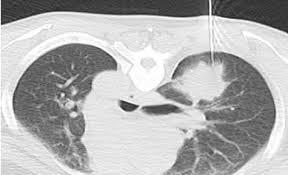

►Chụp chụp cắt lớp vi tính vùng ngực (CT SCAN): giúp phát hiện hình dạng, kích thước, vị trí chính xác của khối u, đánh giá mức độ xâm lấn các cơ quan lân cận như: hạch trung thất, màng phổi, xương sườn, gan…qua đó giúp đánh giá giai đoạn của bệnh.

►Sinh thiết phổi xuyên thành ngực dưới hướng dẫn của CT SCAN ngực: đây là kỹ thuật lấy mẫu mô từ khối u ở phổi qua một kim sinh thiết dưới sự dẫn đường của CT Scan ngực, thường thực hiện ở những u nằm ở ngoại biên mà kỹ thuật nội soi phế quản không thể tiếp cận được để lấy mẫu mô khối u làm giải phẩu bệnh.